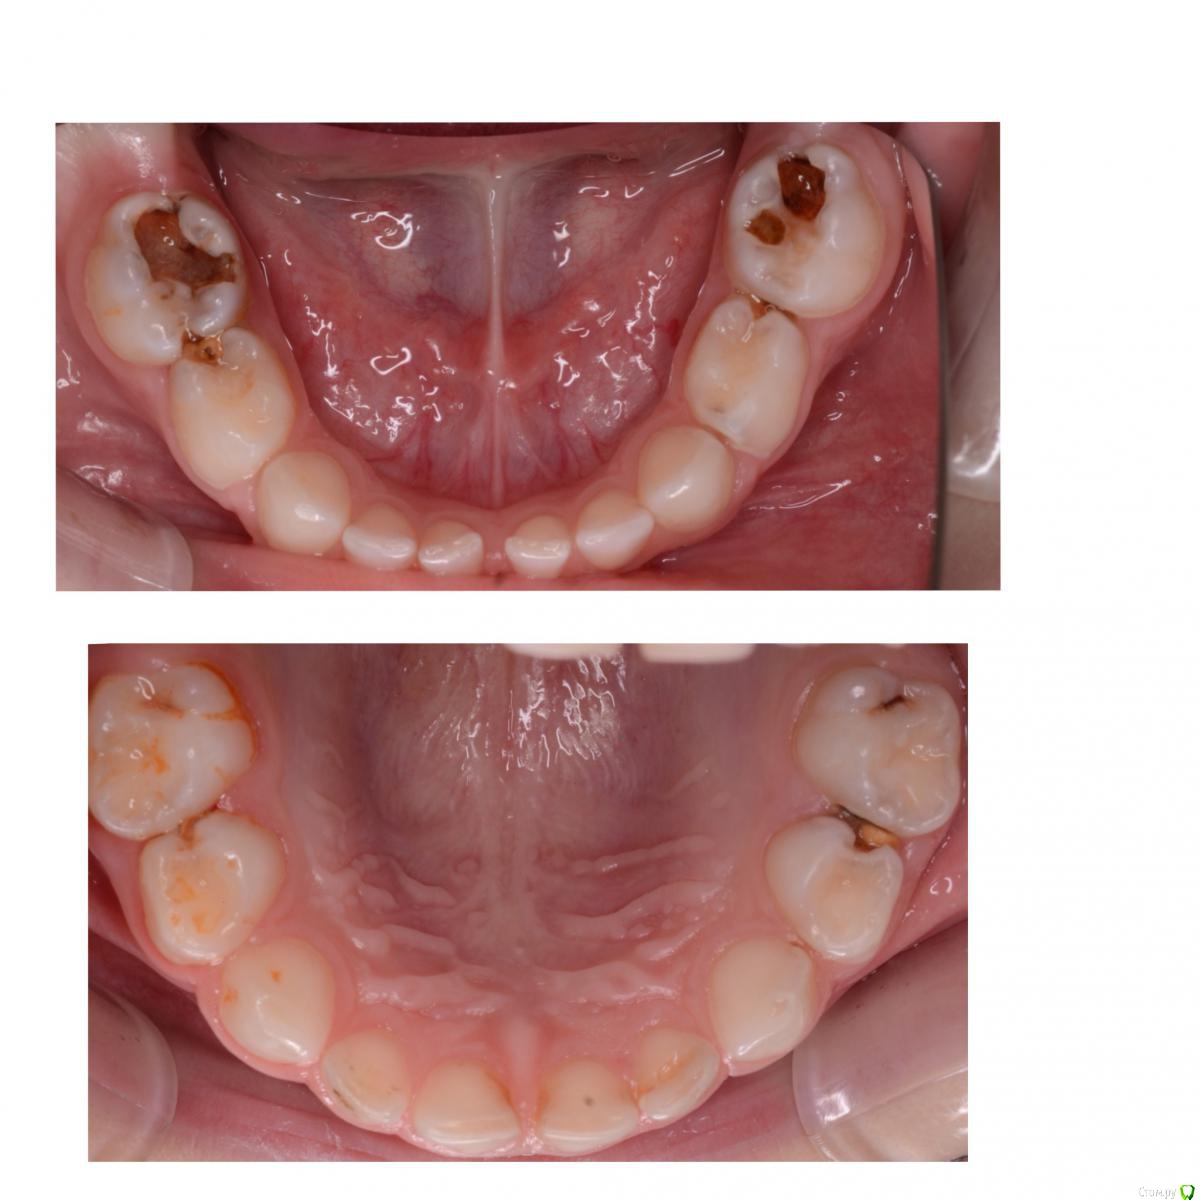

CRAZYDUCK Опубликовано 19 июня, 2018 Автор Поделиться Опубликовано 19 июня, 2018 Обратимый пульпит 7.5 1 Ссылка на комментарий

CRAZYDUCK Опубликовано 23 июня, 2018 Автор Поделиться Опубликовано 23 июня, 2018 Обратимый пульпит 6.4 и 6.5 зубов . 4 Ссылка на комментарий